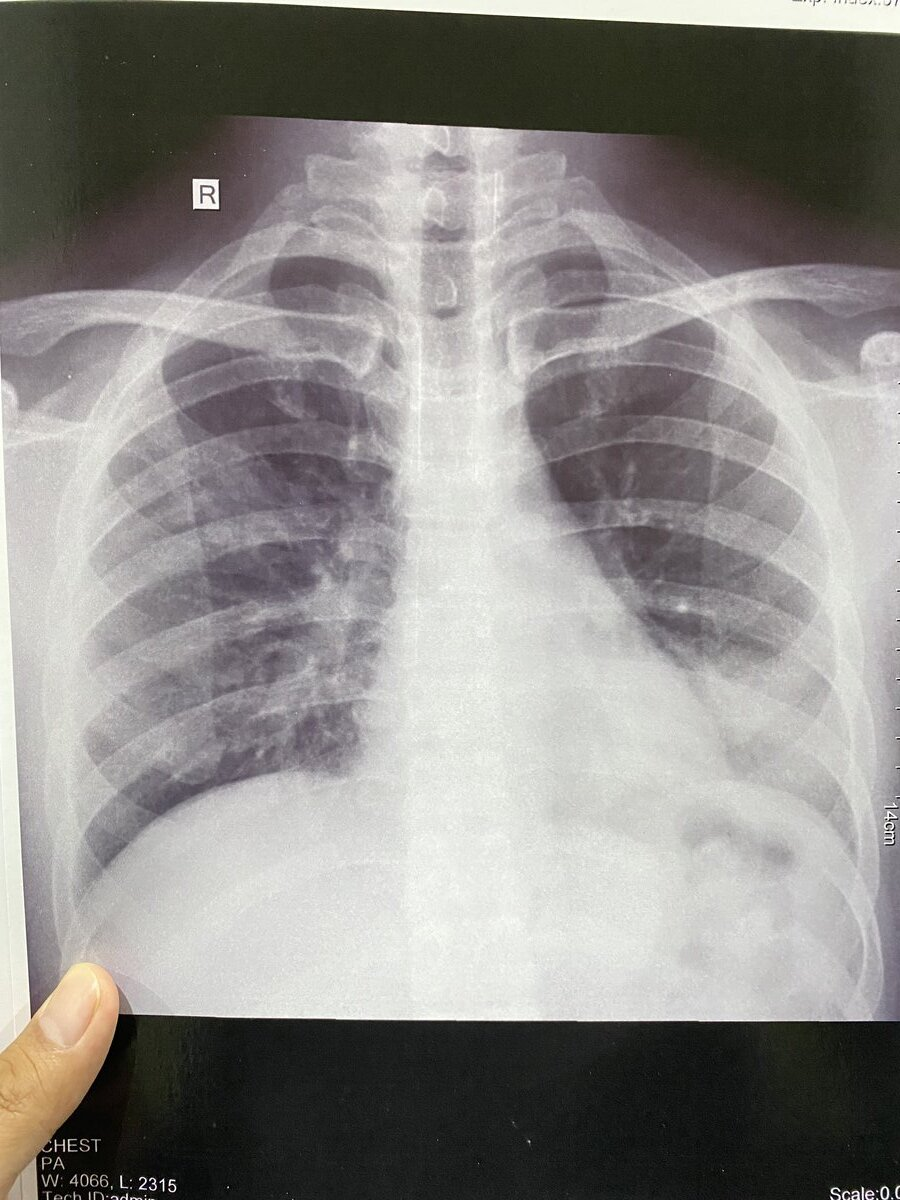

Vonis dokter awal, “gejala TBC”. Namun setelah di screening ternyata riwayat penyakit lama — bronchitis, penyakit yang berhubungan dengan pernapasan, lebih tepatnya ada bakteri diparu-paru.

Hasil ronsen menunjukkan ada flek atau semacam inflamasi pada bagian paru-paru ku. Ini kesekian kalinya setelah 8 tahun kemudian.